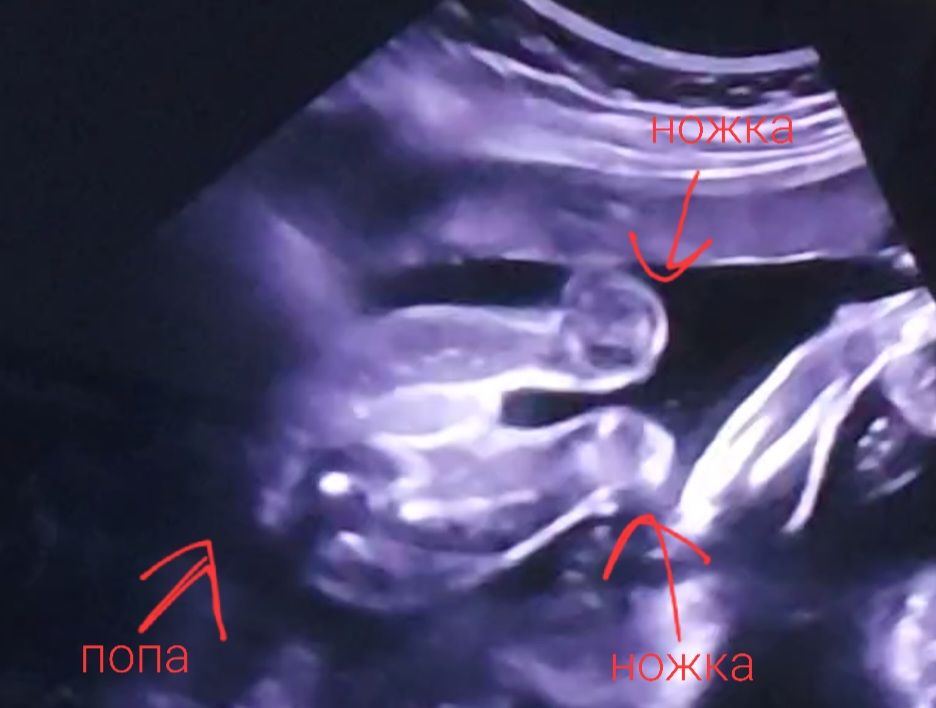

Девочки, кто понимает снимки, покажите пожалуйста писюн на снимке 😁 врач показала в темноте ножки и писюн, а я слепая в спешке не разглядела ничего

Алина, покажите ножку пожалуйста 😅🙏 я даже не понимаю что на снимке, какая часть, какой стороной, полностью ребёнок или нет

Кажется здесь))

как я вижу,вот)) прикрепляю свое узи,чтобы можно было "достроить" вроде видно по лучше😅